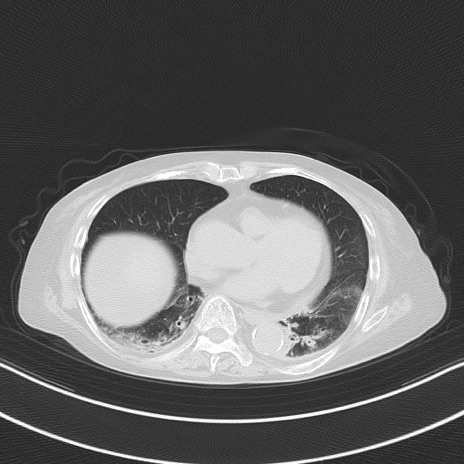

横断像